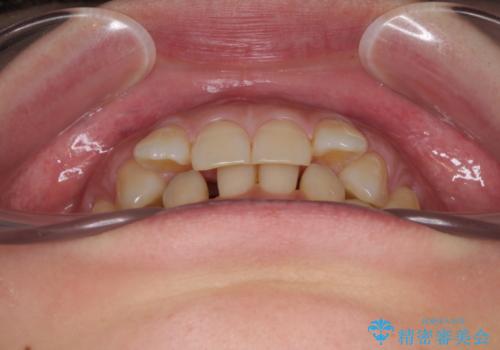

下顎2前歯の欠損 インビザラインによる抜歯矯正

- 下顎前歯欠損による歯列不正を気にして来院された患者様です。

下顎の歯列が小さく、下顎前歯が隠れてしまう過蓋咬合(ディープバイト)であったため、

マウスピースでの抜歯矯正特有の抜歯スペースに向かって奥歯が傾斜する動きが顕著に表れ、ディープバイトは改善されませんでした。